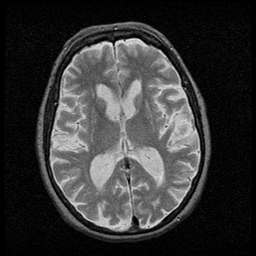

Huntington's Chorea, MR -- Slice #10

[Home][Help][Clinical] Slice 10